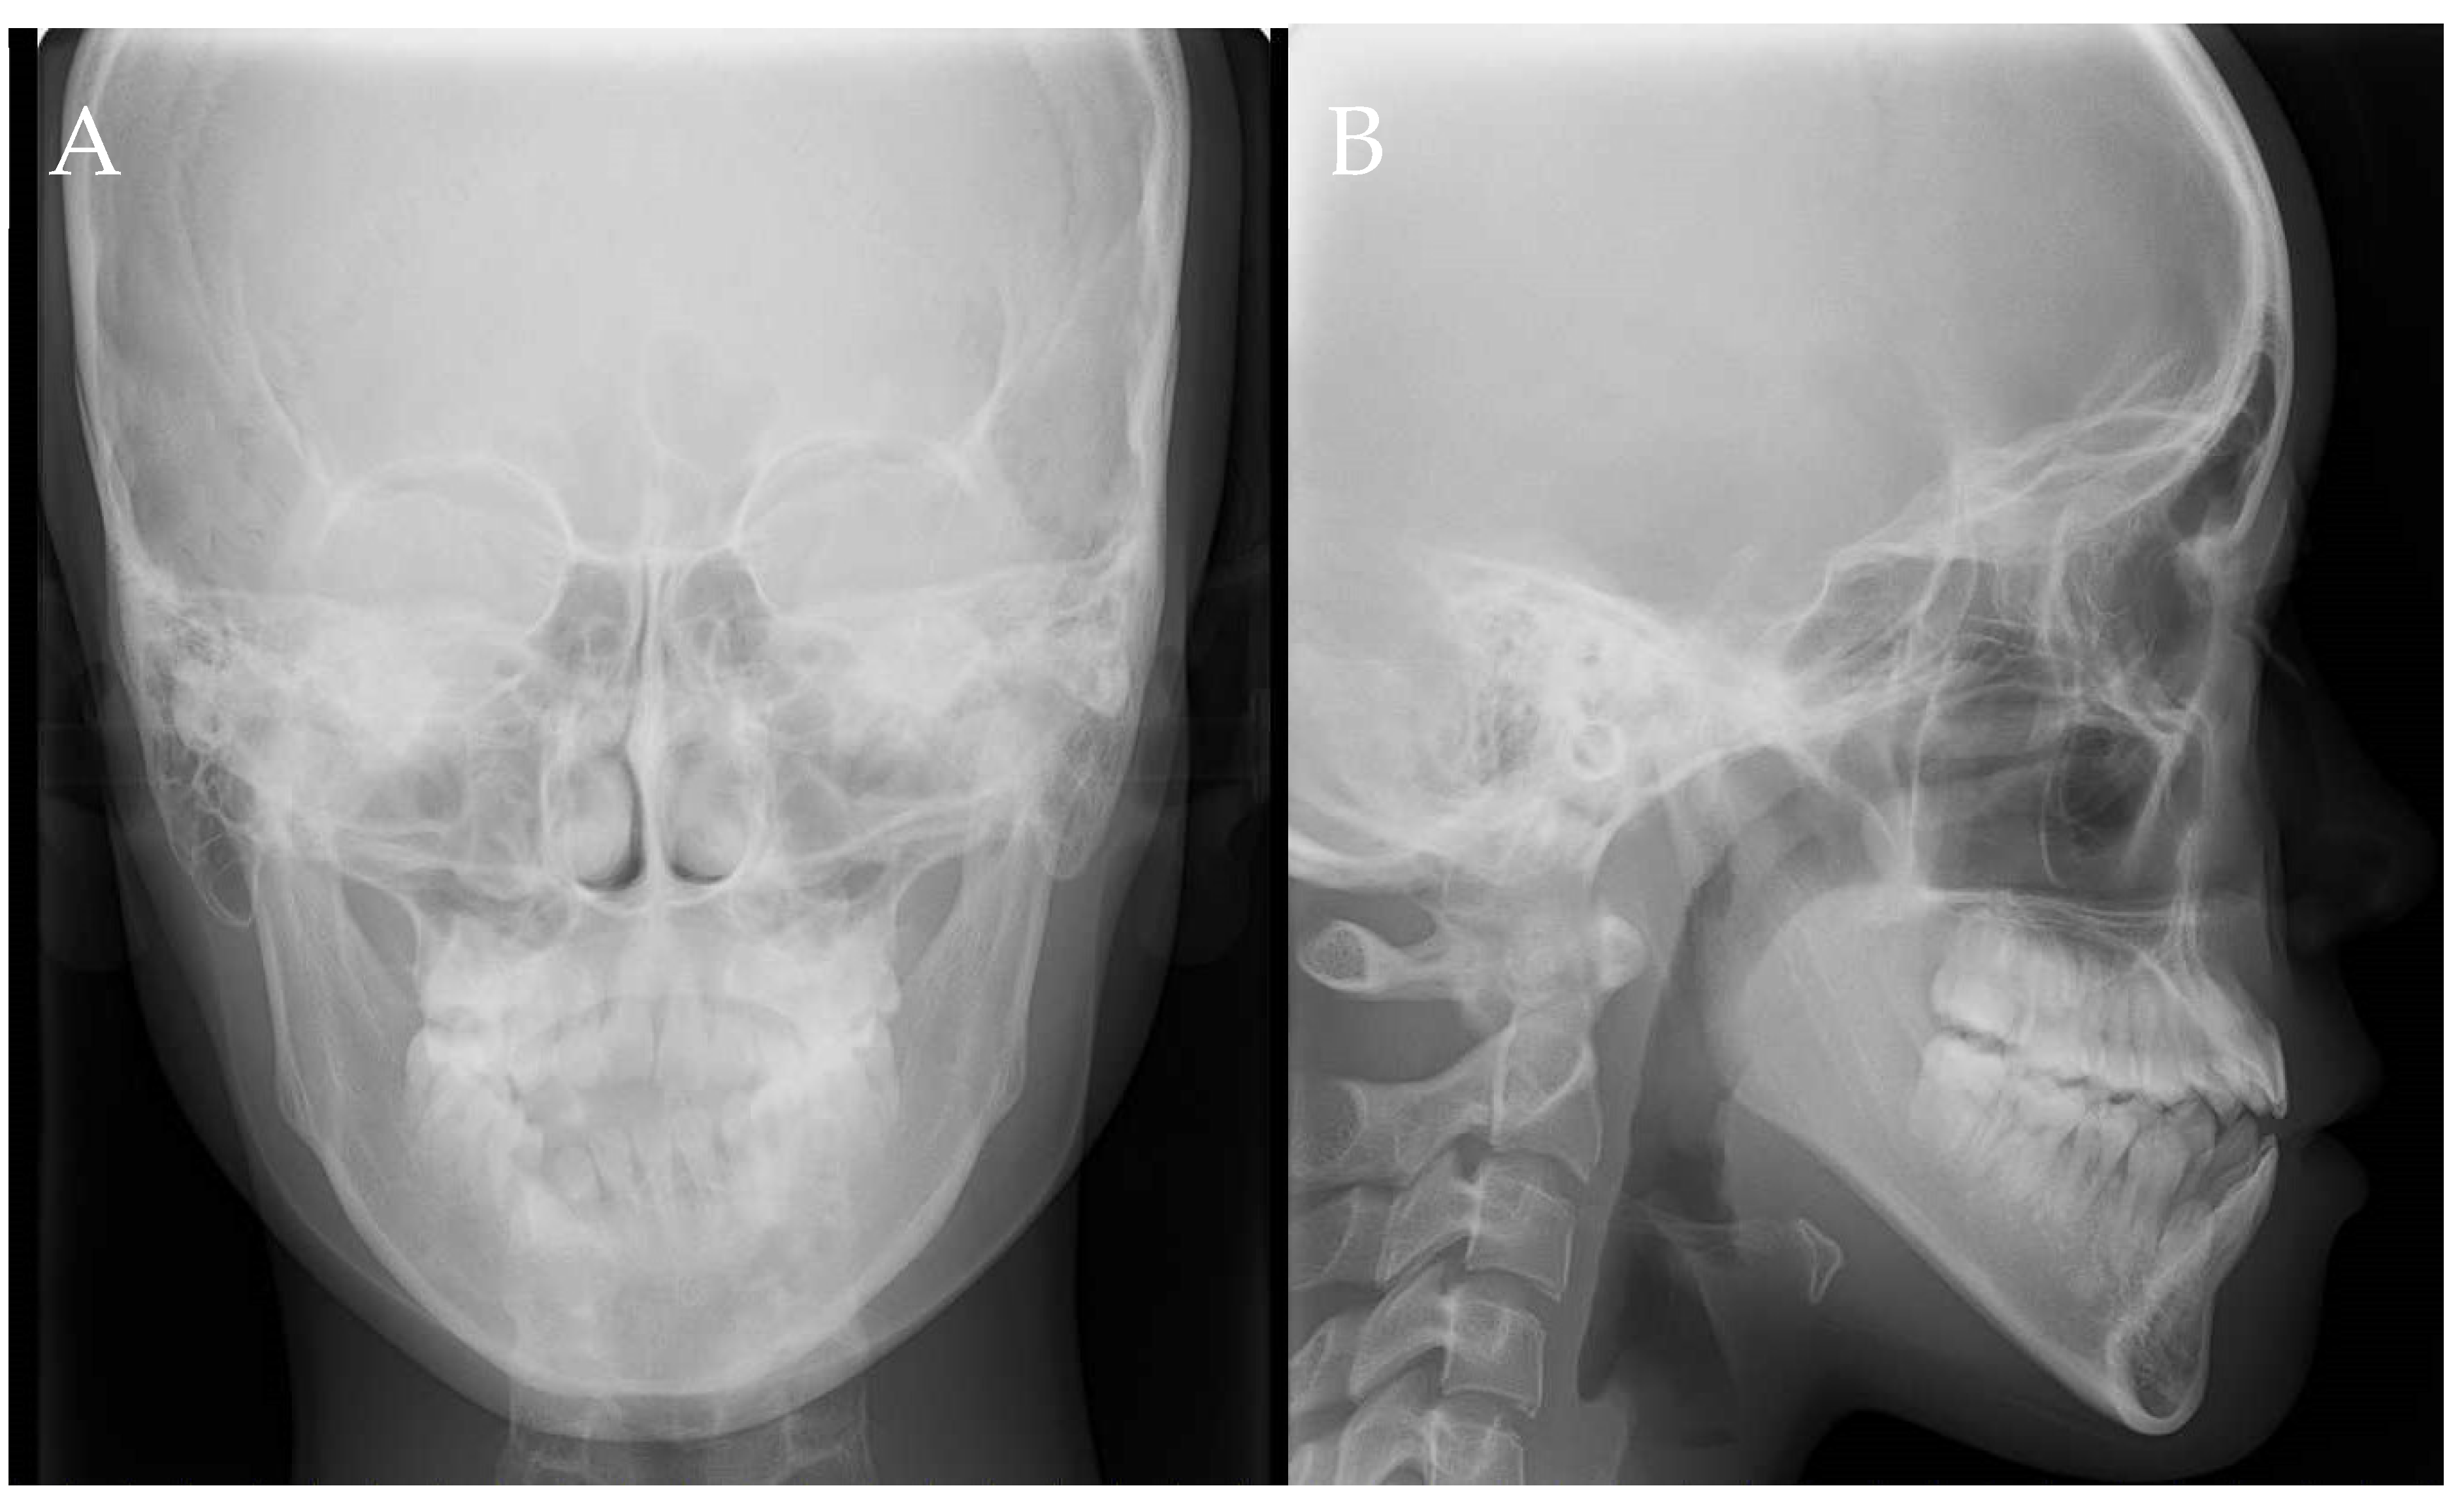

2.6. Imaging Examinations

2.7. Diagnosis